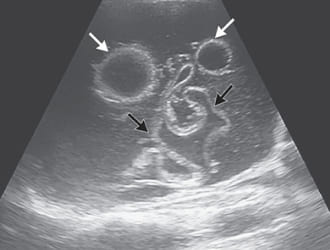

After months of costly medical tests, the diagnosis was finally revealed: a parasitic infection. Astonishingly, about 67% of Juan's body was infested with parasites. They were everywhere! I was stunned and puzzled about their origin. Our home is always immaculate, cleaned two to three times a week. I'm meticulous about buying quality products and thoroughly cleaning them. It was hard to believe that all these symptoms were due to a parasitic infection!

Desperate for answers, I sent Juan's test results to the Laboratory of Parasitic Diseases in the USA. Their response was alarming:

The statistic that 850,000 people in the Philippines die annually without knowing that parasites are the cause of their death is both alarming and a critical public health concern. Parasites are indeed "invisible killers," lurking in everyday items like fish, meat, water, and even fruits and vegetables purchased from supermarkets or markets.